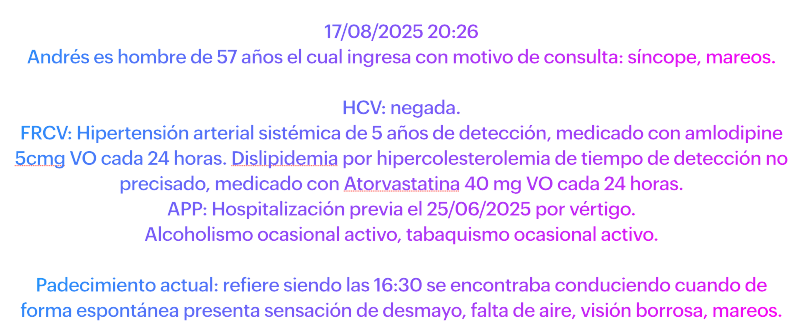

Y también deberíamos poder abordar a este paciente: